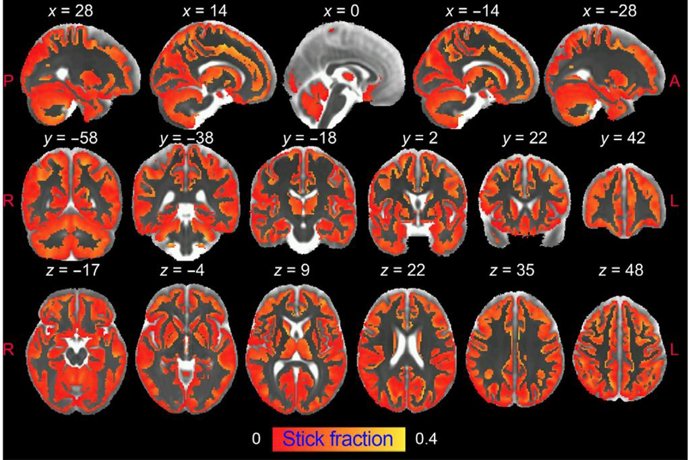

Frente a estos inconvenientes, la resonancia magnética ponderada por difusión tiene la capacidad única de obtener imágenes de la microestructura cerebral in vivo de forma no invasiva y con alta resolución, al capturar el movimiento aleatorio de las moléculas de agua en el parénquima cerebral para generar contraste en las imágenes de resonancia magnética.

En este estudio, los investigadores del Instituto de Neurociencias (CSIC-UMH) han desarrollado una "estrategia innovadora" que permite obtener imágenes de la activación de la microglía y de los astrocitos en la materia gris del cerebro mediante resonancia magnética ponderada por difusión (dw-MRI).

"Es la primera vez que se demuestra que la señal de este tipo de resonancia magnética (dw-MRI) puede detectar la activación microglial y astrocitaria, con huellas específicas para cada población de células. Esta estrategia que hemos utilizado refleja los cambios morfológicos validados post mortem por inmunohistoquímica cuantitativa", señalan los especialistas en un comunicado.

Este trabajo ha logrado demostrar también el valor traslacional del enfoque utilizado en una cohorte de humanos sanos a alta resolución, "en la que se realiza un análisis de reproducibilidad".

"La asociación significativa con patrones de densidad de microglía conocidos en el cerebro humano apoya la utilidad del método para generar biomarcadores de glía fiables. Creemos que caracterizar, mediante esta técnica, aspectos relevantes de la microestructura tisular durante la inflamación, de forma no invasiva y longitudinal, puede tener un tremendo impacto en nuestra comprensión de la fisiopatología de muchas afecciones cerebrales, y puede transformar la práctica diagnóstica actual y las estrategias de seguimiento del tratamiento de las enfermedades neurodegenerativas", destaca de Santis.